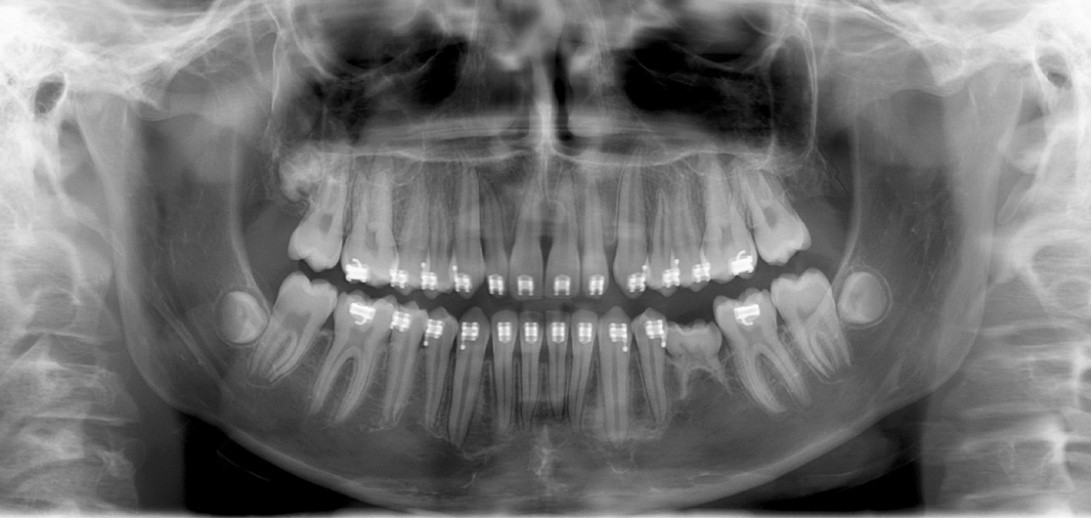

1. (Select ONE OR MORE correct answers)

The radiograph shows evidence of